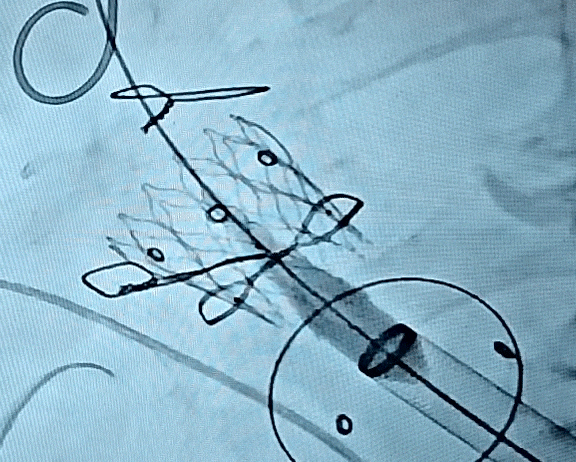

康复大学青岛中心医院林明山教授分享一例“双瓣一站式”高难度VIV病例,深刻展现自膨短瓣在生物瓣衰败VIV中的应用价值。患者83岁男性,于2010年行主动脉瓣置换术、二尖瓣置换术及三尖瓣成形术,现主动脉瓣和二尖瓣生物瓣均出现重度反流,术前超声/CT充分评估后,决定采用经心尖入路,先行主动脉瓣瓣中瓣植入术(TAVR-VIV),顺利送入ScienCrown TAVTA 23mm瓣膜,得益于该款瓣膜短瓣架设计,完全释放后对血流影响小,因此TAVR-VIV术中无需起搏,瓣膜初次释放位置稍浅,部分回收调整瓣膜深度重新释放,即刻造影示瓣膜位置良好,无张力脱钩瓣膜位置稳定,术后TEE示主动脉瓣平均跨瓣压差仅4mmHg。随后行二尖瓣瓣中瓣植入术(TMVR-VIV),经心尖入路植入ScienCrown TAVTF 29mm瓣膜,主动脉根部造影,冠脉显影良好无瓣周漏,术后TEE示二尖瓣平均跨瓣压差仅1mmHg。

TAVR-VIV术后造影